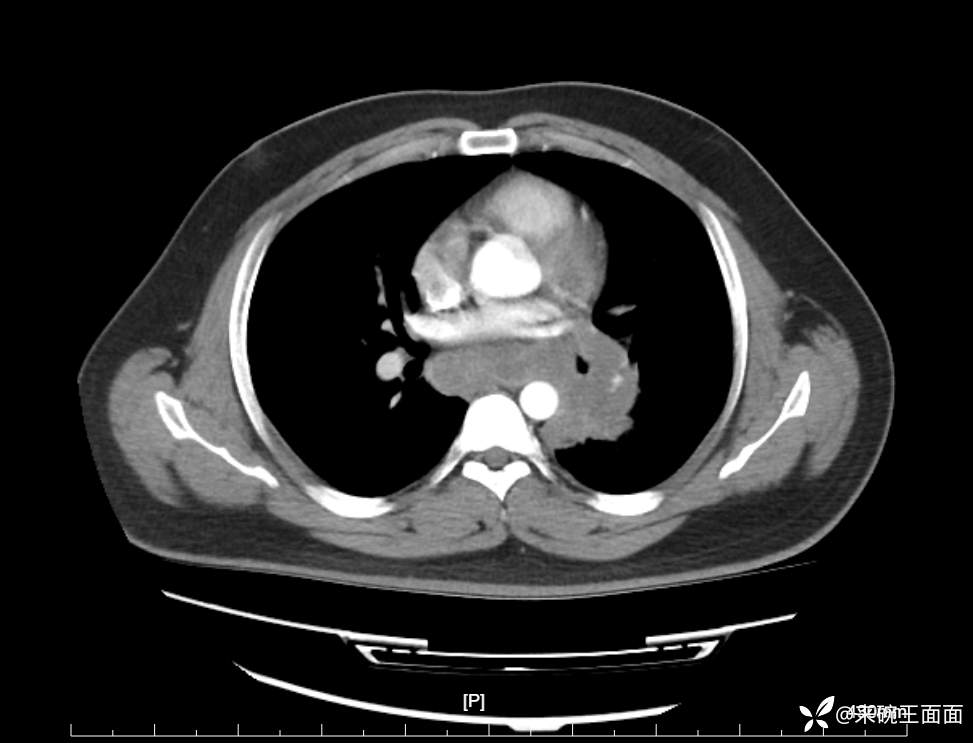

性别:男

年龄:27岁

主诉:胸闷胸痛数月余,休息后可自行缓解,无咯血症状。

个人史:数年吸烟史,具体不详。